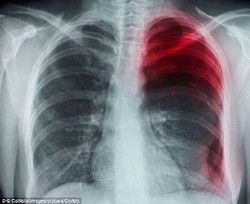

Ini Bedanya Kanker Paru pada Perokok dan Nonperokok

Kanker paru yang menyerang perokok berbeda jenisnya dengan yang menyerang nonperokok. Jika seseorang merokok, maka orang tersebut menghadapi risiko ganda untuk terserang kedua jenis kanker paru tersebut.